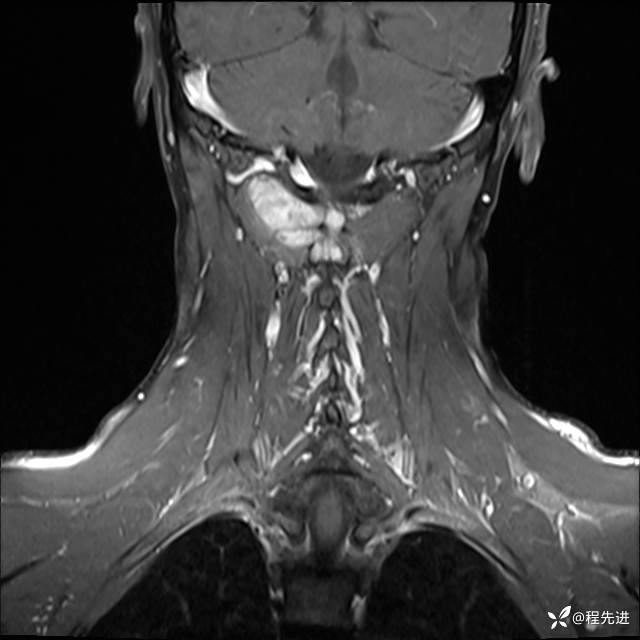

MRI平扫+增强:

T1增强: